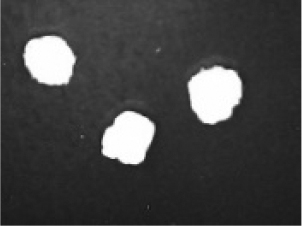

In addition to the disintegration endpoint studied using the USP disintegration apparatus, the pellets disintegrated into particles of various sizes when evaluated at a static position. A few drops of water were placed on the pellets on the opaque surface. A USB digital microscope (China) was connected to a computer to capture the disintegration process. Images were captured from the beginning until the pellet disintegrated or exploded into small fragments. Pellet images were acquired every 30 seconds. for formulations containing polyplasdone XL 10 and croscarmellose sodium.

Disintegration was evaluated at room temperature under static conditions. The camera captured images every 30 s ( Table 9), illustrating that MCC pellet X3 with mannitol and PEG 400 did not disintegrate. Within 120 s, cracks appeared in P5 pellets containing mannitol, PEG, and PPXL. As seen in the C4 pellets, they begin to explode into many fragments within 30 s. Moreover, the CP12 pellets containing PEG 400, mannitol, CCS, and PPXL began to explode into many loosely linked particles after 60 s, which quickly separated under the oscillating motion of the USP disintegration equipment. The photographs are compatible with the results mentioned above for the USP disintegration device. When the temperature was increased to 37°C, the disintegration caused the split into tiny fragments.

Table 9. Camera capture of pellet disintegration at different time intervals.

Pellet # 0 sec. 30 sec. 60 sec. 90 sec. 120 sec.

X3c9c3975f-9288-4951-a800-a8e9fc463382_GRA58.gif c9c3975f-9288-4951-a800-a8e9fc463382_GRA59.gif c9c3975f-9288-4951-a800-a8e9fc463382_GRA60.gif c9c3975f-9288-4951-a800-a8e9fc463382_GRA61.gif c9c3975f-9288-4951-a800-a8e9fc463382_GRA62.gif

P5c9c3975f-9288-4951-a800-a8e9fc463382_GRA63.gif c9c3975f-9288-4951-a800-a8e9fc463382_GRA64.gif c9c3975f-9288-4951-a800-a8e9fc463382_GRA65.gif c9c3975f-9288-4951-a800-a8e9fc463382_GRA66.gif c9c3975f-9288-4951-a800-a8e9fc463382_GRA67.gif